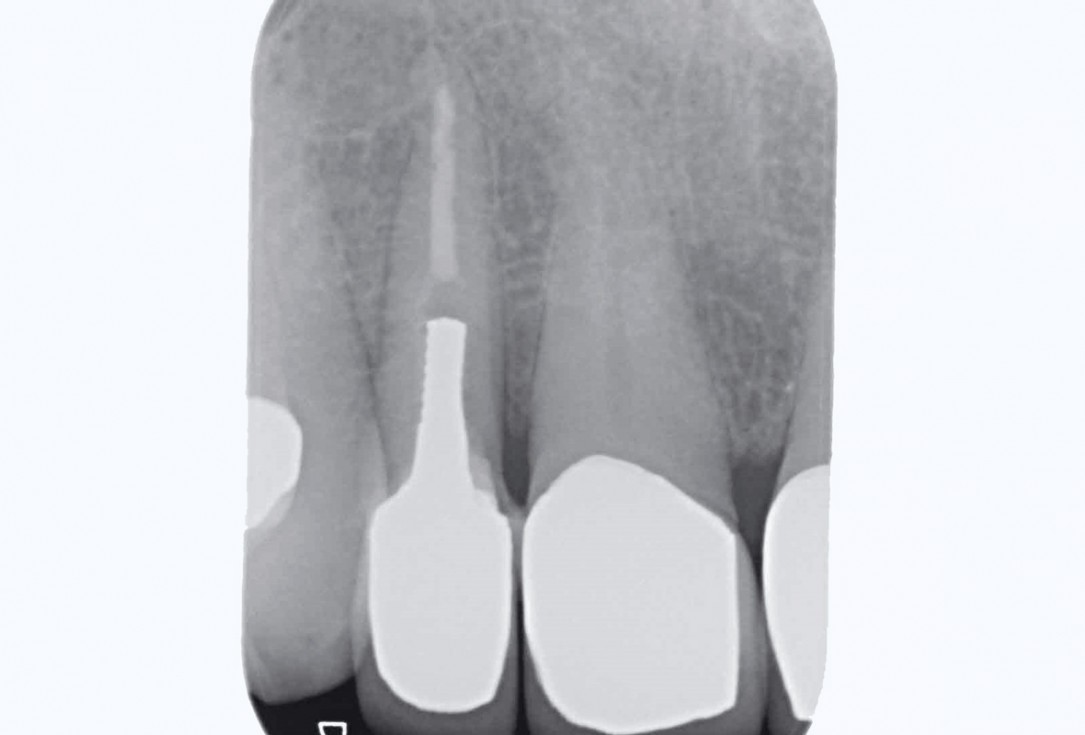

2/19 - Initial situation: x-rayBone augementation with maxresorb® - Dr. R. Cutts